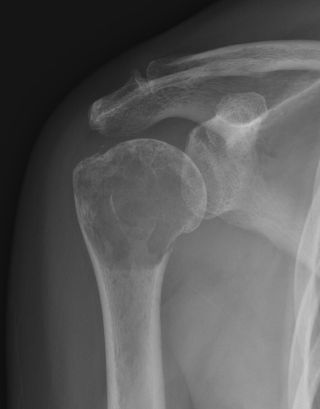

X-ray

Need > 50% bone loss to see

Remember to xray entire bone

- especially NOF fracture

- need to bypass all lesions

Lytic / Sclerotic / Mixed

1. Purely lytic - lung / kidney / breast / thyroid / GI

2. Sclerotic - prostate / breast / bladder / GI / lung

3. Mixed - breast / prostate / lung / bladder